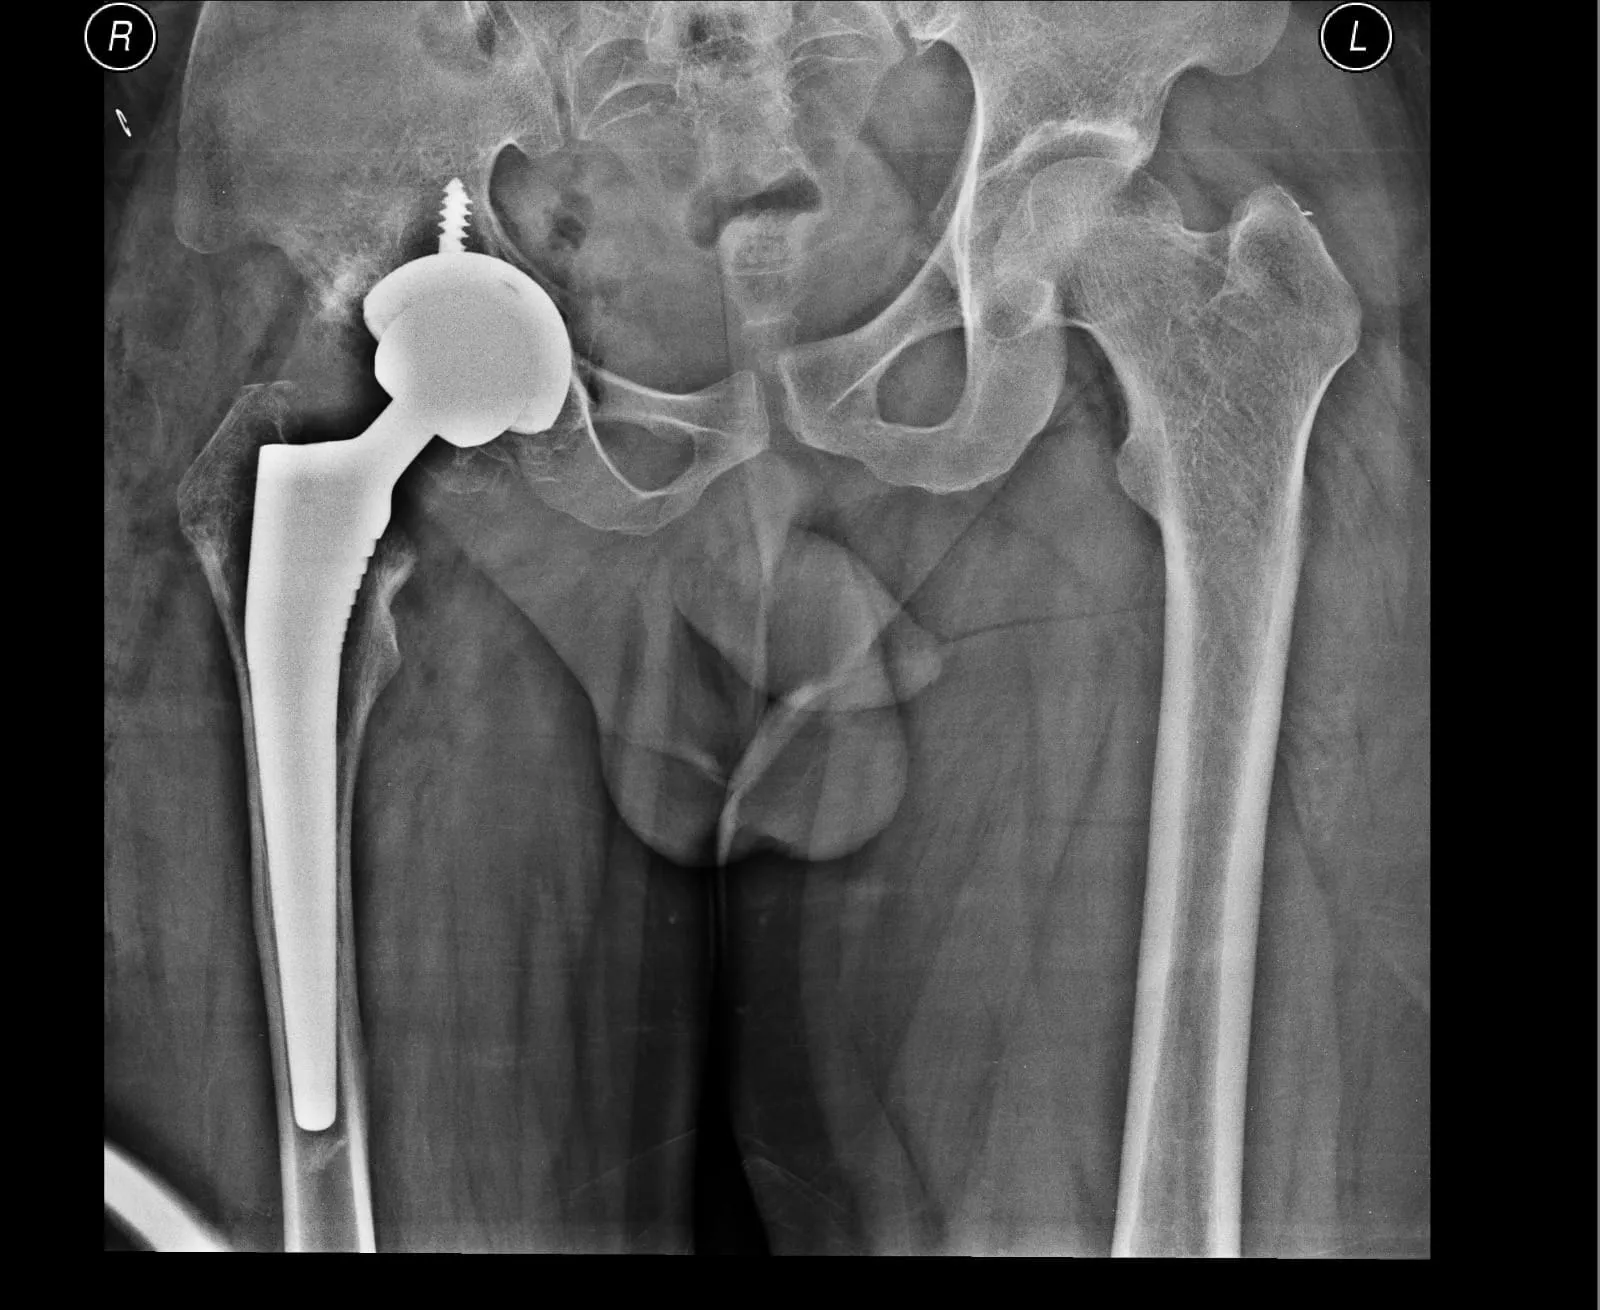

Quality and affordable healthcare has long been the essence in the field of medical sciences & treatment. Every patient expects an early diagnosis and a planned approach to treatment procedures with affordability and access to quality healthcare. Knee replacement, Hip replacement, Fracture treatment are being done by Dr.P.Sankaralingam at very affordable costs without compromising on quality.

Dr.P.Sankaralingam M.S(ortho)., DNB (ortho).,MNAMS is an experienced senior consultant Orthopaedic surgeon who does about 350 joint replacement surgeries per year in addition to treatment of Trauma cases.

• Hip & Knee Replacement and Revision Surgeries